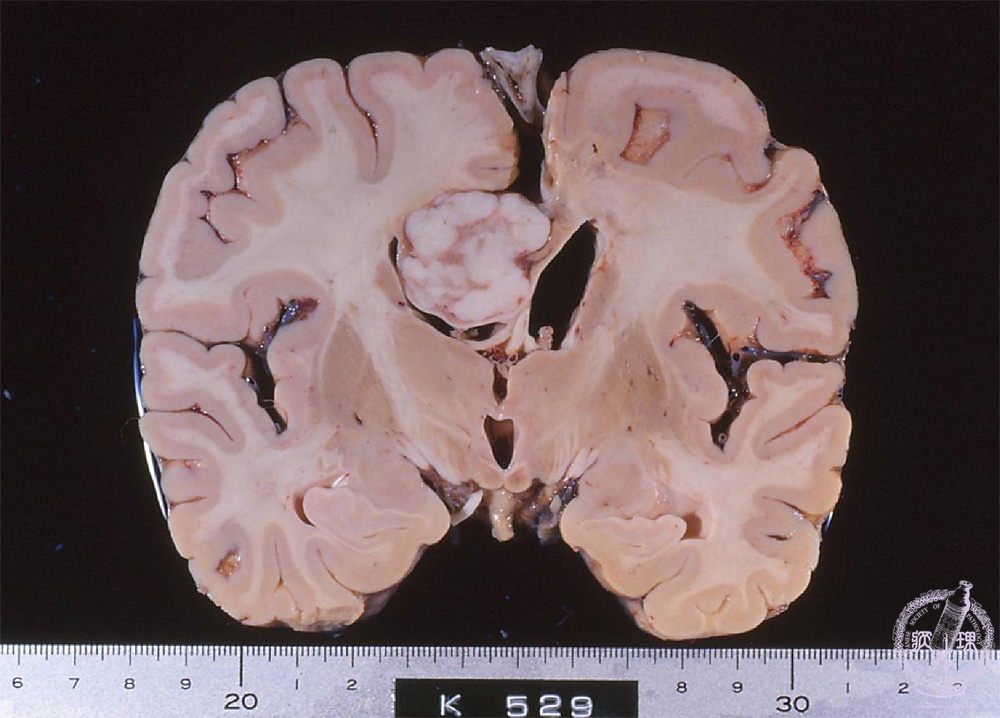

- ★(9)Meningioma

Macroscopic findings: Meningioma arising in the cerebral falx (red circle). The well-circumscribed whitish tumor compressed right lateral ventricle downword